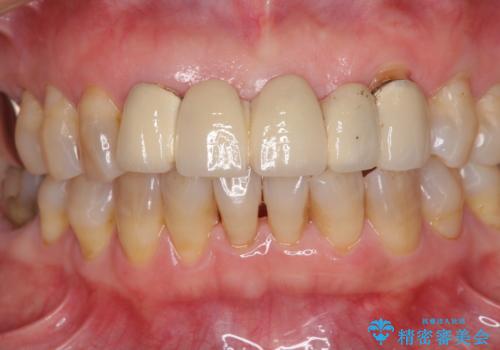

- アンバランスな色や形、歯肉ラインの黒い縁が目立ってしまったブリッジの作り直しを希望して来院された患者様です。

装着されていたブリッジは、支台となっている歯と欠損している歯で色が大きく異なっていましたが、オールセラミックとしたことで、全体的に色調の整った仕上がりとなりました。

歯肉ラインがきれいに整い、患者様には大変満足していただきました。